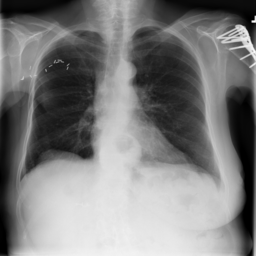

We used the NIH Chest X-ray 14 [73] dataset to conduct our experiments. This dataset consists of labeled chest X-ray images, from over unique patients corresponding to 14 common thoracic disease types, including atelectasis, cardiomegaly, effusion, infiltration, mass, nodule, pneumonia, pneumothorax, consolidation, edema, emphysema, fibrosis, pleural thickening, and hernia. The dataset is divided into training, validation, and testing sets, containing , . and images, respectively444We followed the dataset splits in https://github.com/zoogzog/chexnet/tree/master/dataset. Our experiments were designed to examine and compare four training methods:

Figure 7 samples real and GAN-generated images. The first column presents real images, the second column GAN-generated unsupervised, and the third GAN-generated supervised. The GAN-generated images may successfully fool our colleagues with no medical knowledge. However, as reported in [63], the GAN-generated labeled chest X-ray images must be screened by a team of radiologists to remove erroneous data (with respect to diagnosis knowledge). Without domain knowledge, incorrectly labeled images may be introduced by GANs into the training pool, which would degrade classification accuracy.

| Real | GAN unsupervised | GAN supervised |